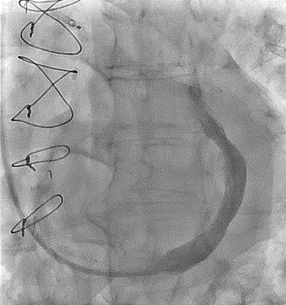

After the right transjugular puncture and introducer implantation, the coronary sinus (CS) was catheterized (Figure, A; Video 1). A CSR was advanced to the targeted implantation site in the mid-segment of the CS. The guiding catheter was then retracted, and the balloon was inflated to expand the CSR at the implantation site. After deflation, the balloon was retrieved. During the extraction of the deflated balloon, under fluoroscopy, we observed device migration into the right atrium while being attached at the tip of the catheter (Figure, B; Video 2). To snare the reducer, a 14-French sheath was advanced in the right femoral vein. We attempted to keep the wire inside the stent, but the prothesis migrated to the left pulmonary artery without the possibility of recovering it using the lasso technique (Figure, C; Video 3). We decided to implant a second CSR more distally in the CS (Figure, D; Video 4).

The patient received dual antiplatelet therapy for 3 months. At his 8-month follow-up, he reported a reduction of angina severity without any complications and agreed to leave the device in place.

Though uncommon, migration during implantation is one of the most-reported complications of CSR implantation.1 If the snare technique fails to capture the embolized prothesis, or if the prothesis migrates to a distal branch of a pulmonary artery, the CSR may be left in place distally.